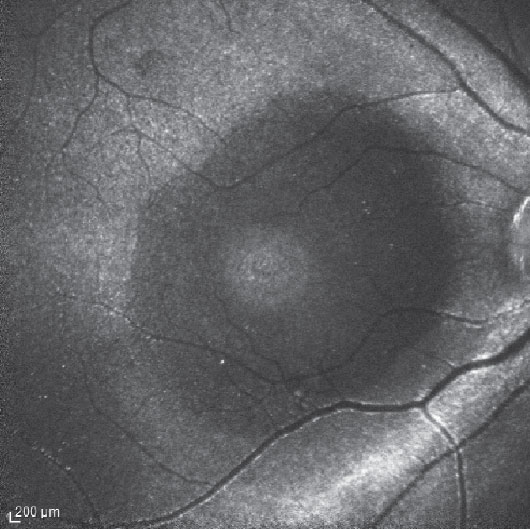

Figure 1. Indocyanine green fluorescence imaging in a patient following pars plana vitrectomy and internal limited membrane removal for a macular hole shows hyperfluorescence originating from the residual ILM. The dark circular area of relative hypofluorescence corresponds to the area of removed ILM. A smaller area of hyperfluorescence corresponds to the base of the MH. |